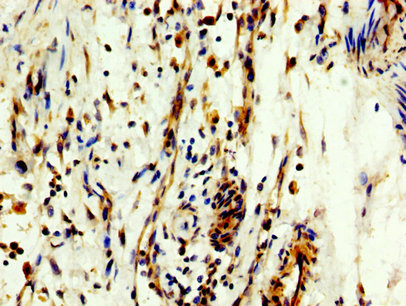

IHC image of CSB-PA015387LA01HU diluted at 1:300 and staining in paraffin-embedded human bladder cancer performed on a Leica BondTM system. After dewaxing and hydration, antigen retrieval was mediated by high pressure in a citrate buffer (pH 6.0). Section was blocked with 10% normal goat serum 30min at RT. Then primary antibody (1% BSA) was incubated at 4°C overnight. The primary is detected by a biotinylated secondary antibody and visualized using an HRP conjugated SP system.